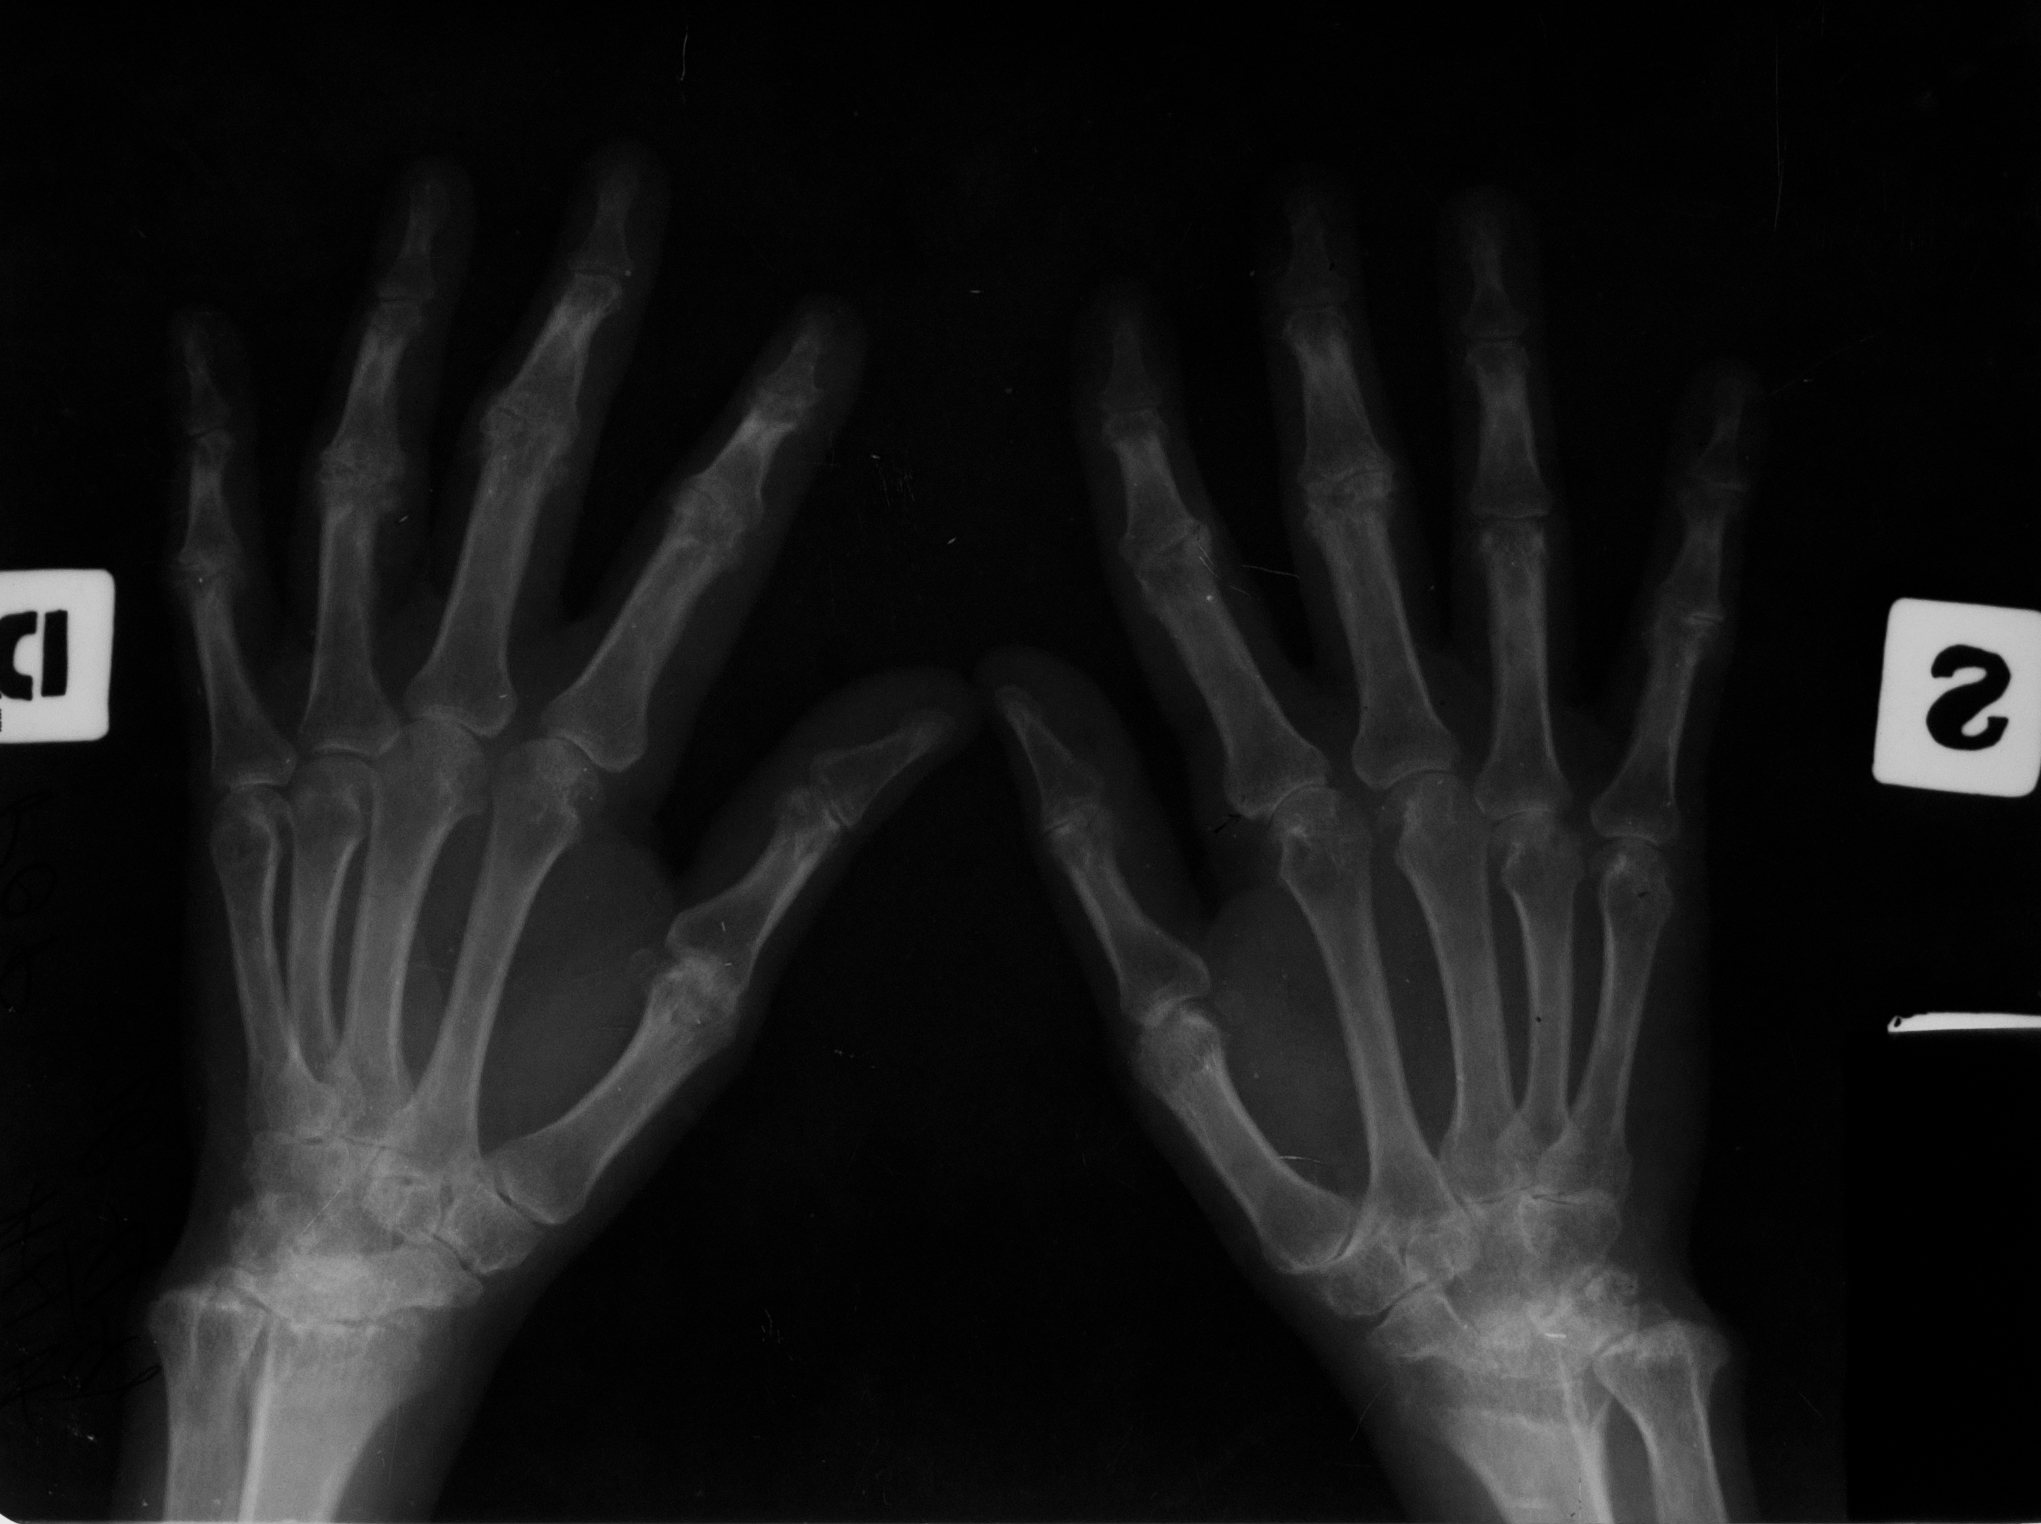

Osteoporoza in bandă, care e stadiul incipient (stadiul I) de poliartrită reumatoidă

Radiografie comparativa de maini, in care se vede o transparenta crescuta a extremitatilor metacarpienilor (adica a capetelor metacarpienilor, respectiv a bazelor falangelor)

Stadiul II spre III de poliartrita reumatoida

Radiografie comparativa de maini, cu osteoporoza accentuata, cu spatii disparute la nivelul oaselor carpiene si lize semnificative la nivelul spatiilor articulare interfalagiene proximale (deci bazele falangelor, respectiv capetele falangelor proximale), lize marginale cu disparitie de spatii articulare – stadiul 2 spre 3 de poliartrita reumatoida

MODIFICĂRI DE STADIUL 3 DE POLIARTRITĂ REUMATOIDĂ

Osteoporoză accentuată,absenta spațiilor articulare și distrucția severă ale oaselor carpiene,lize,osteolize și subluxații ale falangelor una pe cealaltă cu derivație pe cubitus(derivație cubitală)